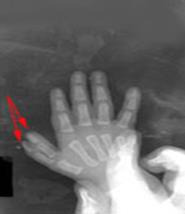

Рис.8 Больная В., 16 лет со сложной формой синдактилии.

Рентгенограмма до лечения.

Рис.9. Результат лечения больной В., рентгенограмма после лечения.